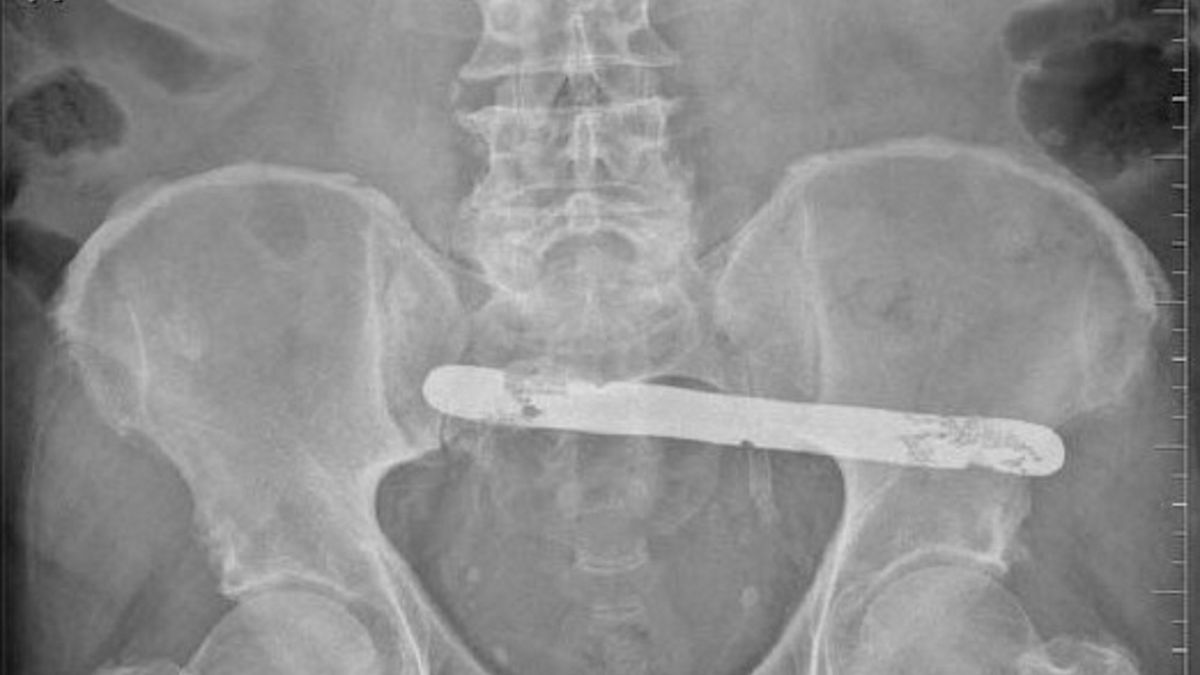

W sprawie pacjenta z Podkarpacia interweniował Rzecznik Praw Pacjenta. Mężczyzna przeszedł operację usunięcia pęcherzyka żółciowego w jednym ze szpitali w tym regionie. Po półtora roku dowiedział się, że nosi w brzuchu metalową szpatułkę o wielkości 19 cm x 2 cm.

Rzecznik Praw Pacjenta ujawnił niektóre szczegóły sprawy. Pacjent został wypisany ze szpitala bez wskazania, co właściwie ma dalej zrobić ze szpatułką. Nie otrzymał nawet wyjaśnień dotyczących ewentualnej operacji usunięcia ciała obcego. Placówka odsuwała się od odpowiedzialności tłumacząc, że przedmiot mógł zostać po poprzednim zabiegu, który pacjent miał w latach 60. (ten był również przeprowadzany w tym samym szpitalu).

Sprawa znalazła swój finał w sądzie. Udowodniono, że szpatułka pozostała w organizmie po ostatniej operacji, gdyż wykonano przed nią diagnostykę jamy brzusznej, która nic nie wykazała. Pacjentowi przyznano odszkodowanie w wysokości 40 tysięcy zł. Rzecznik uznał jednak, że kwota ta jest zbyt niska i wniósł apelację. Sąd Apelacyjny w Rzeszowie potwierdził to i podwyższył zadośćuczynienie do 65 tysięcy złotych.